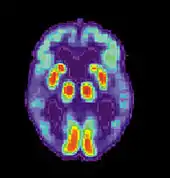

Alzheimer's disease is characterised by loss of neurons and synapses in the cerebral cortex and certain subcortical regions. This loss results in gross atrophy of the affected regions, including degeneration in the temporal lobe and parietal lobe, and parts of the frontal cortex and cingulate gyrus.[96] Degeneration is also present in brainstem nuclei particularly the locus coeruleus in the pons.[97] Studies using MRI and PET have documented reductions in the size of specific brain regions in people with AD as they progressed from mild cognitive impairment to Alzheimer's disease, and in comparison with similar images from healthy older adults.[98][99]

Alzheimer's disease is usually diagnosed based on the person's medical history, history from relatives, and behavioral observations. The presence of characteristic neurological and neuropsychological features and the absence of alternative conditions is supportive.[119][120] Advanced medical imaging with computed tomography (CT) or magnetic resonance imaging (MRI), and with single-photon emission computed tomography (SPECT) or positron emission tomography (PET) can be used to help exclude other cerebral pathology or subtypes of dementia.[121] Moreover, it may predict conversion from prodromal stages (mild cognitive impairment) to Alzheimer's disease.[122]